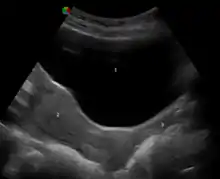

Vaginal health can be assessed during a pelvic examination, along with the health of most of the organs of the female reproductive system.[97][98][99] Such exams may include the Pap test (or cervical smear). In the United States, Pap test screening is recommended starting around 21 years of age until the age of 65.[100] However, other countries do not recommend pap testing in non-sexually active women.[101] Guidelines on frequency vary from every three to five years.[101][102][103] Routine pelvic examination on adult women who are not pregnant and lack symptoms may be more harmful than beneficial.[104] A normal finding during the pelvic exam of a pregnant women is a bluish tinge to the vaginal wall.[97]

Pelvic exams are most often performed when there are unexplained symptoms of discharge, pain, unexpected bleeding or urinary problems.[97][105][106] During a pelvic exam, the vaginal opening is assessed for position, symmetry, presence of the hymen, and shape. The vagina is assessed internally by the examiner with gloved fingers, before the speculum is inserted, to note the presence of any weakness, lumps or nodules. Inflammation and discharge are noted if present. During this time, the Skene's and Bartolin's glands are palpated to identify abnormalities in these structures. After the digital examination of the vagina is complete, the speculum, an instrument to visualize internal structures, is carefully inserted to make the cervix visible.[97] Examination of the vagina may also be done during a cavity search.[107]